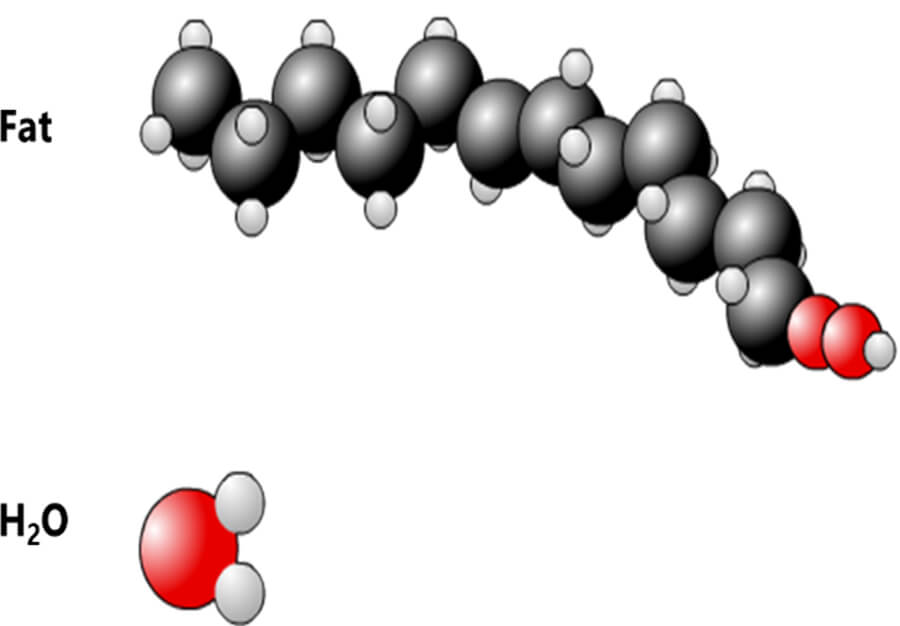

Consider the fact that the human body is more than 65% water. All tissue has some amount of water in it. Take the fat cell for instance, it is made of 80% water. The water molecule has two hydrogen atoms for every 1 oxygen atom – that’s why it’s H2O, right?

As we have mentioned, the human body is comprised of more than 65% water. Consider the water molecules to be the dancers in the nightclub. Because it is a large population, it will give a strong signal. We will learn more about this later. For now, let’s closely examine a water molecule and a fat molecule.

Here we see 2 molecules: Fat and Water. The hydrogen atom, represented by the smaller circles, is present in large quantities in both. Of course, fat and water are not the only molecules in the human body containing hydrogen. As mentioned earlier, Hydrogen is the third most abundant atom in the human body. There is some amount of water and/or fat, in all tissue in the body. There are two hydrogen atoms in every water molecule and there are as many as 12 hydrogen atoms in a molecule of fat, depending on the type of fat. Again, because it is so abundant in the body it will give off a strong signal.